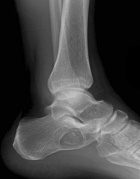

37 year old male reports a one year history of increasing pain and discomfort in his left heel. He reports that his pain is exacerbated with activity, relieved by rest. It is a 9/10 pain. He reports that at times it is constant and also occasionally awakens him at night. He denies any history of trauma. He is currently taking Motrin for the pain.